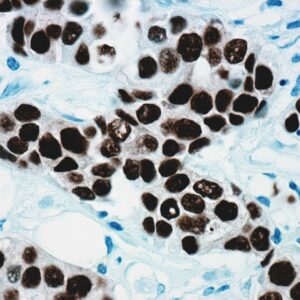

The fluoresceinated Hsa-miR-365A-3P probe has been designed from mature human miR-365A-3P sequence. This Hsa-miR-365A-3P identifies miR-365A-3P sequences in formalin-fixed, paraffin-embedded human tissues and freshly prepared frozen tissues by in situ hybridization. This probe does not react with normal human mRNA or nuclear DNA present in tissues.